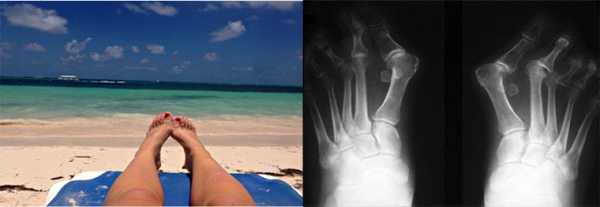

Вальгусное искривление - самая известная и самая широко распространенная причина деформации I пальца стопы. Обусловлена слабостью связок стопы, сочетается с поперечным плоскостопием. Чаще встречается у женщин среднего и старшего возраста. Большой палец отклоняется кнаружи, в результате между ним и I плюсневой костью образуется угол.

Со временем деформация нередко прогрессирует. Нарушения эстетики стопы усугубляются фиброзными разрастаниями, омозолелостями и сопутствующим артрозоартритом. Второй палец изгибается, становится молоткообразным, накладывается на первый. После длительного пребывания на ногах и в фазе обострения артрозоартрита деформация несколько усугубляется из-за отека мягких тканей.

Одновременно нередко прогрессирует Hallux Valgus (деформация I плюснефалангового сустава, которую обычно называют «косточкой» или «шишкой» на стопе). В результате сочетанной деформации II палец стопы иногда ложится на изогнутый кнаружи I палец, что негативно влияет на функции стопы и существенно затрудняет подбор обуви.

Косточка на большом пальце ноги, тяжёлый случай

Часто пациенты обращаются на запущенных стадиях заболевания, когда происходит не только смещение большого пальца кнаружи с образованием «косточки» в области головки первой плюсневой кости, но также появляется молоткообразная деформация 2-3-4 пальцев, внутреннее отклонение 5 пальца, появление косточки в области головки 5 плюсневой кости, возникновение болей под головками 2-3 плюсневой кости.

Клинический пример, пациентке 75 лет, деформация у неё начала прогрессировать с 20 летнего возраста. Что же произошло за это время?